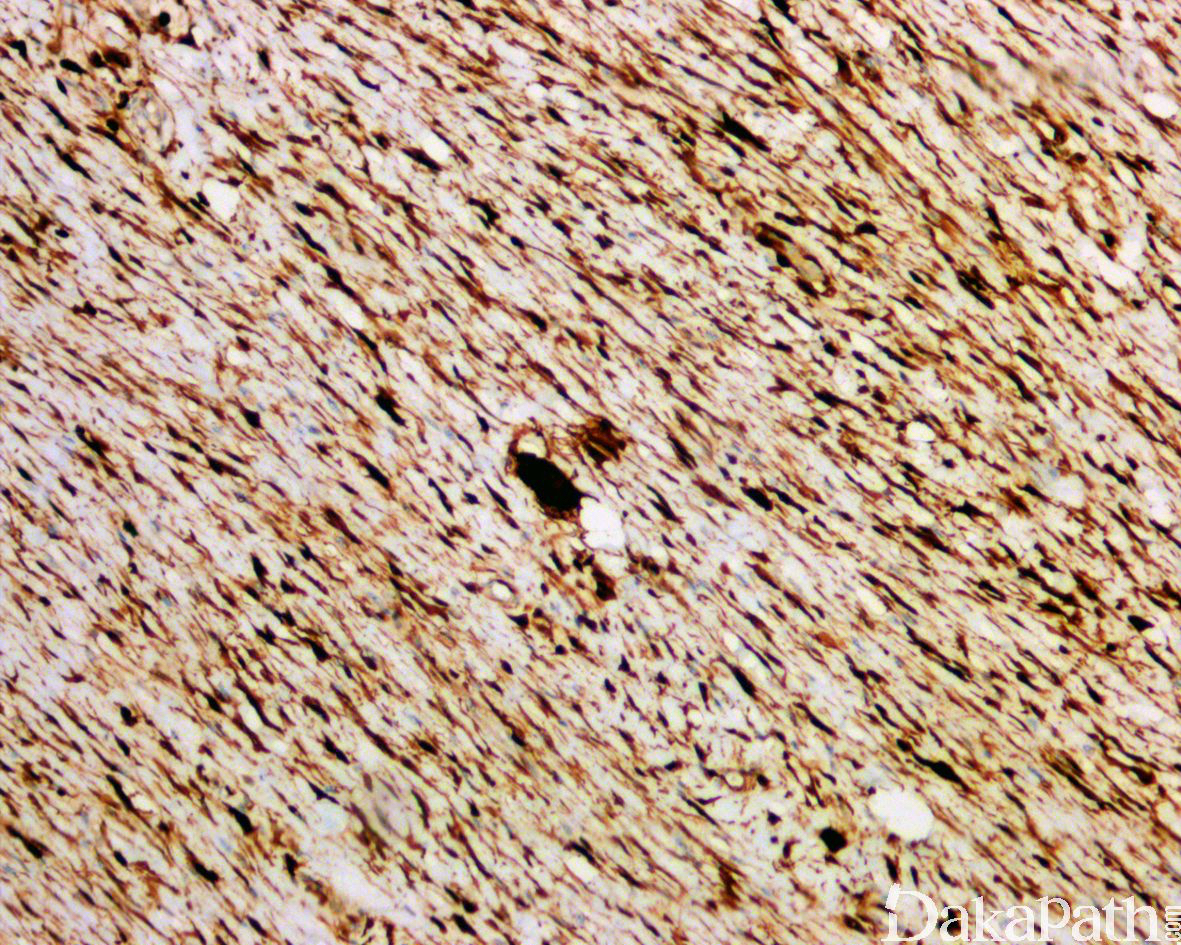

免疫组织化学染色,绝大多数的 DDLPS 弥漫强表达 p16 蛋白(核和质表达),是诊断 DDLPS 最敏感的标志物,但缺乏特异性,许多与之形态学相似的肿瘤,特别是高级别肿瘤(如平滑肌肉瘤和肉瘤样癌等)亦可弥漫表达 p16。由于 DDLPS 一致性的存在 12q14-15 区域的扩增和过表达,而 MDM2 蛋白和 CDK4 蛋白的强表达与相应的基因扩增存在高度的一致性,因此免疫组织化学染色 MDM2 和 CDK4 的共表达(均为弥漫核表达)对于诊断 DDLPS 具有较大的帮助。在与 ALT/WDLPS 之外的其他类型的脂肪源性肿瘤的鉴别诊断中,联合应用 p16. MDM2 和 CDK4 对于诊断 DDLPS 具有高度的敏感性和特异性,93%的 DDLPS 表达上述 3 个标志物中的至少 2 个,72%表达全部 3 个标志物。但在 DDLPS 与非脂肪源性的肿瘤鉴别诊断时,上述 3 个标志物的特异性则明显不够;此时,应用荧光原位杂交(FISH)检测 MDM2 基因的扩增对于诊断 DDLPS(在适当的组织学背景下)具有高度的特异性和敏感性,尤其是在小活检标本、未见典型的 ALT/WDLPS 成分、低级别去分化和少见特殊类型的 DDLPS 诊断时更是如此。MDM2 基因的扩增目前普遍认为是诊断 ALT/WDLPS 和 DDLPS 的金标准,需要指出的是,MDM2 基因扩增并非 ALT/WDLPS 和 DDLPS 所特有,其他常见存在 MDM2 基因扩增的肿瘤还包括低级别中央型骨肉瘤、骨旁骨肉瘤以及原发的心脏内膜肉瘤等。约半数左右的 DDLPS 可局灶或弥漫表达 CD34,去分化成分一般不表达 S100 蛋白,伴有肌纤维母细胞分化者可表达 SMA 和 MSA 或结蛋白[23],伴有横纹肌和平滑肌分化者可分别表达 MyoD1 和 H-caldesmon,具有脑膜上皮瘤样漩涡特征的 DDLPS 可表达 SMA 和 Claudin-1 提示其肌纤维母细胞或神经束膜分化的特征。新近发现,约 6%的 DDLPS 可见 H3k27me3 的表达缺失易与恶性外周神经鞘膜瘤(MPNST)混淆,约 11%的 DDLPS 可见 STAT6 基因扩增从而局灶或弥漫表达 STAT6 易误诊为孤立性纤维性肿瘤(SFT)。